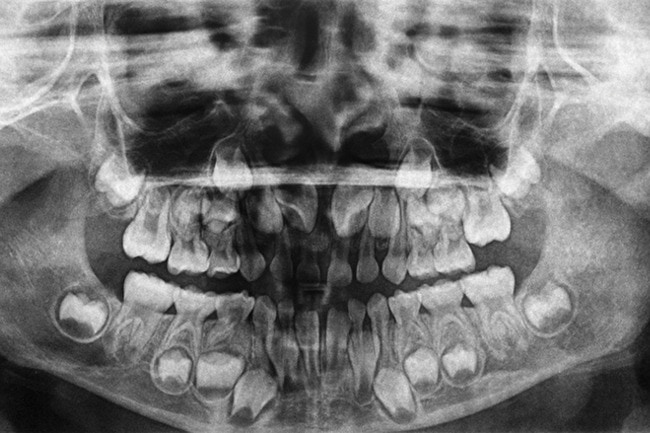

【閲覧注意】10年間歯を磨かなかった人間はこうなる(ガチ画像)

gif_animation 10年間歯を磨かなかった人間はこうなる1枚の画像。(※ TOP画はイメージ)